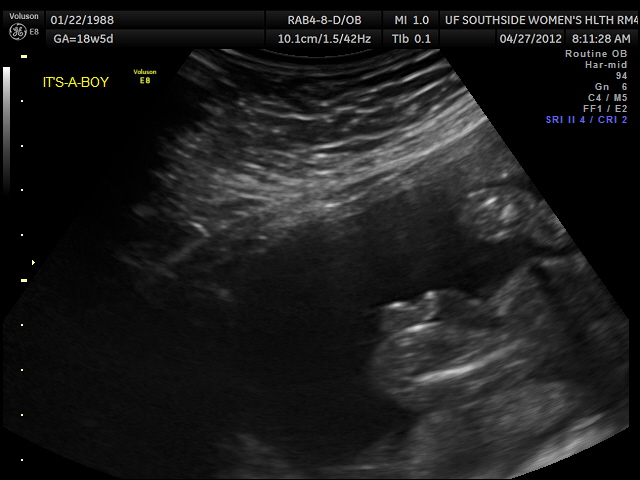

The clinic on base had an ultrasound machine in the exam room so the midwife would show us the baby each time. Every single time I held my breath after she turned on the monitor until I heard my baby's heartbeat. I was a bit paranoid. One week, she said if the baby would cooperate, she might could see if it was a he or a she! We got really excited but there was no cooperation from baby's end. So we went home a little disappointed. Zachary asked if there was anywhere we could go and get a ultrasound done so I did some research and found a place for the next day. We were so excited. I was convinced my motherly instincts were telling me it was a girl and Zachary would not budge- he didn't care which one and he didn't have a feeling either way- he was just excited to find out. We played games on the way to the office- if we saw more blue cars than red, it would be a boy... if the place where on the left instead of the right, it would be a girl. We were just so giddy. We got there and I got on the table... we looked at his brain and his heart and his arms and legs... and then she went to the mystery area and said, "Oh! Okay... are you ready?" And we said yes and she said "definitely a boy." Zachary was a very proud dad at that moment. I really was shocked but never disappointed. We called all of our parents and let them know and I felt a new bond with my baby boy just knowing he was a he.

| 18 Week Anatomy Scan- It's a Boy! |